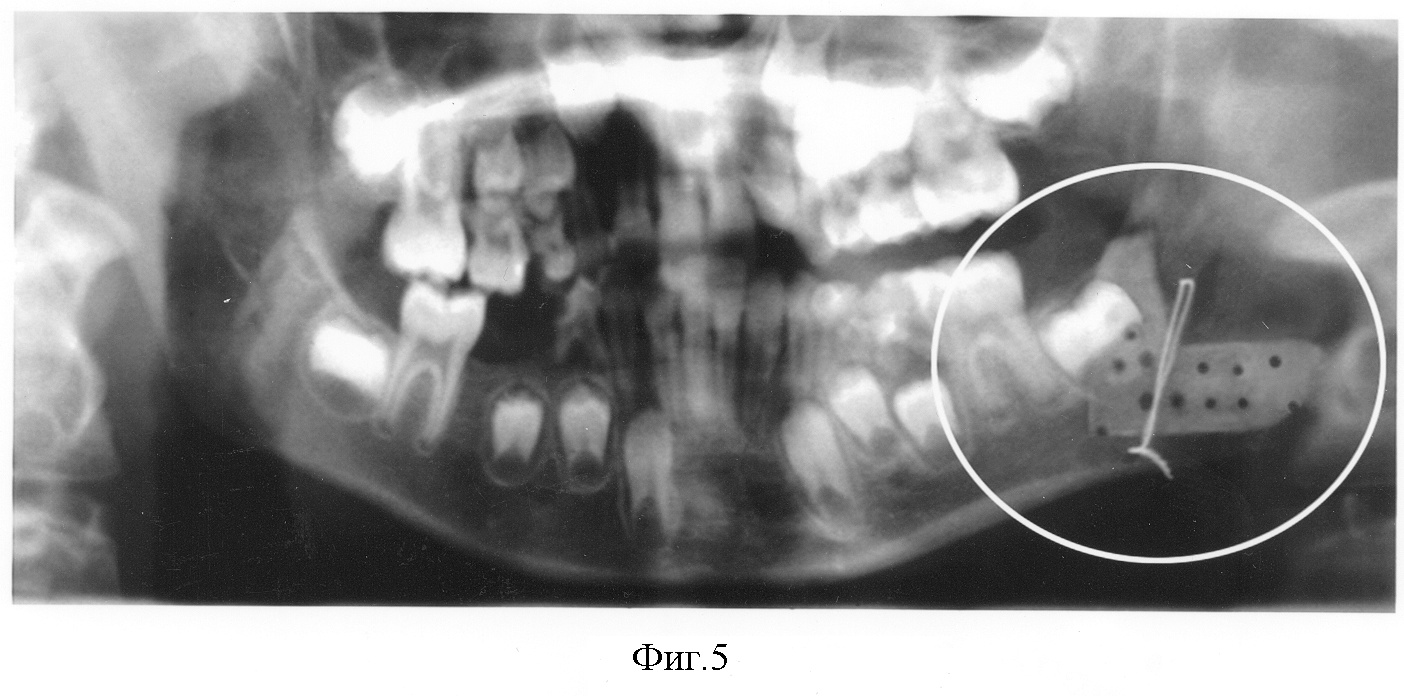

На фиг.5 представлена ортопантомограмма, расположение перфорированного аллотрансплантата в области тела, угла и ветви нижней челюсти слева и фиксация костным швом.